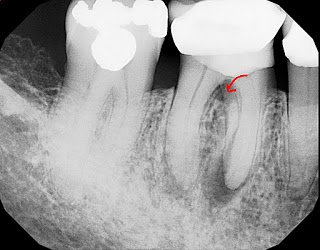

This patient went to her new dentist for a broken restoration on #30. Decay was found encroaching on the pulp chamber and she was referred for root canal therapy. She is asymptomatic. #31 was treated 2 years ago by another endodontist, no microscope. The anatomy appears to be very challenging. A history of symptoms of cold sensitivity and throbbing pain prior to the previous treatment indicate that #31 was likely diagnosed as irreversible pulpitis preoperatively.

Treatment on #30 was completed at today’s visit and treatment options for #31 were discussed. Restoratively, the case is compromised with a crown on a buildup with voids. Additionally, retreatment of the mesial root is going to be challenging if not impossible. If, as it appears, the distal root is the primary source, retreatment may be successful. One alternative, if retreatment is not successful, is to place spacers to loosen the tooth and then try an intentional reimplantation. Apical surgery is difficult to impossible in this location with such long roots (25mm working length on #30).